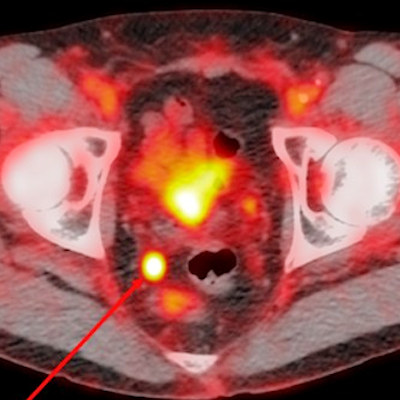

Two abstracts cover the firm's PET/CT imaging agent for prostate cancer, PyL, and the third abstract relates to Lantheus' radiopharmaceutical therapeutic for metastatic castration-resistant prostate cancer, 1095.